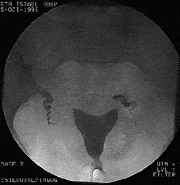

צילום רחם תקין: מילוי תקין של חלל הרחם עםמעבר ופיזור תקינים